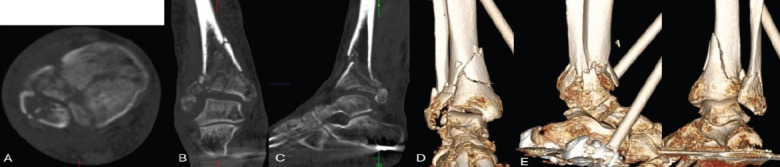

Case report: A 64-year-old female with a history of chronic obstructive pulmonary disease, hypertension, and a significant smoking history presented with a right tibial pilon and distal fibula fracture following a fall down the stairs. Due to her medical comorbidities and poor soft tissue envelope, she was at high risk for complications with ORIF. After discussing multiple treatment options, she elected to proceed with a tibiotalar intramedullary nail to optimize function while minimizing surgical morbidity. The procedure was performed using a suprapatellar approach, and an 8mm nail was inserted to preserve bone stock and future surgical options. Postoperatively, she progressed well, achieving full fracture healing by 9 months with minimal pain and functional independence. She declined further surgical intervention for hardware removal or ankle fusion, reporting satisfaction with her outcome.